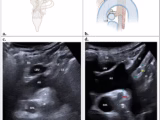

Agreement of IVC Diameter Measurements via Subcostal and Transhepatic POCUS Views

Santiago Beltramino; Giuliano Gaudenzi; Jhon Mauricio Rojas; Agustín Manchado Bruno - This study evaluates the concordance between two views in ventilated and non-ventilated patients, categorizing the IVC as small, intermediate, or large.